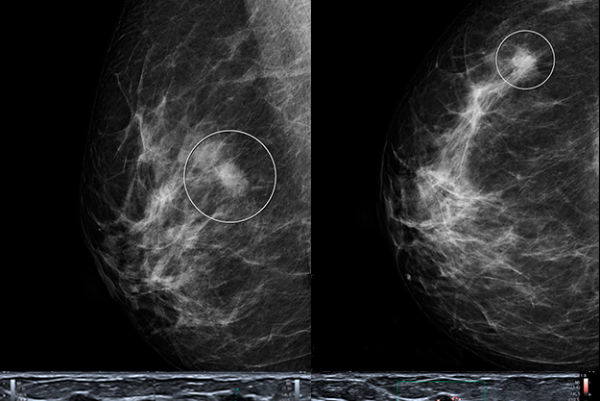

A lo largo de la formación aprenderás los criterios diagnósticos básicos de las lesiones mamográficas benignas y malignas para interpretar los resultados. Así mismo, conocerás la aportación del Doppler al diagnóstico de las lesiones mamarias Podrás integrar los hallazgos ecográficos con el resto de estudios mamarios para aplicarlos conjuntamente en el manejo de la paciente. Adquirirás nociones básicas de los hallazgos mamarios en Resonancia Magnética y entenderás el funcionalismo del ovario y su diversa patología.

Unidad 2- Interpretación radiológica en patología mamaria: BIRADS. Guillermo Santandreu

Unidad 3- Nódulos y densidades asimétricas. Lilian Casas

Unidad 4- Microcalcificaciones. Dario Cassina

Unidad 5-Otras alteraciones mamográficas asociadas a un cáncer de mama. Natalie Korsun

Unidad 6- Ecografía mamaria: Indicaciones y anatomía ecográfica. Beatriz Navarro